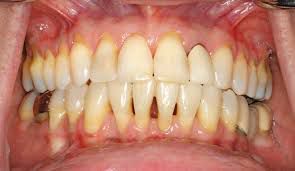

Your gums may recede for a number of reasons. Gum recession causes include: Brushing too hard or too aggressively. Dental plaque or tartar buildup. Periodontal disease. Trauma or injury to your gum tissue. Abnormal tooth positioning (misalignment). Smoking or chewing tobacco use. Lip and tongue piercings.